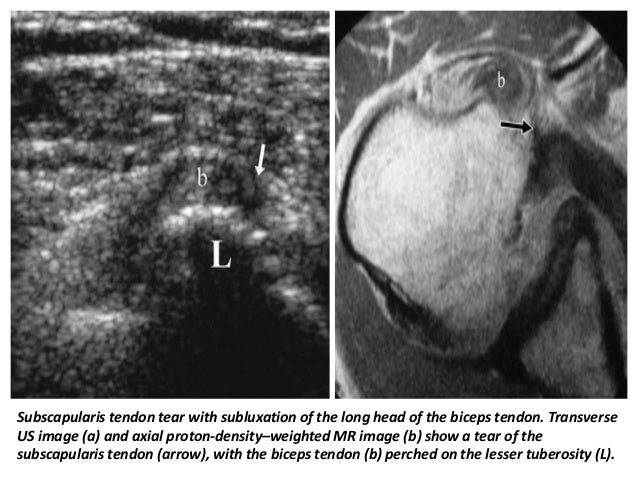

32. 32. Subscapularis tendon tear with subluxation of the long head of the biceps tendon. Transverse US image (a) and axial proton-density–weighted MR image (b) show a tear of the subscapularis tendon (arrow), with the biceps tendon (b) perched on the lesser tuberosity (L).